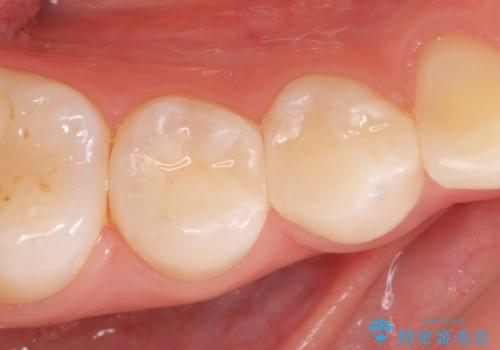

不適合なクラウンのやりかえ

セラミッククラウンによる奥歯のむし歯治療